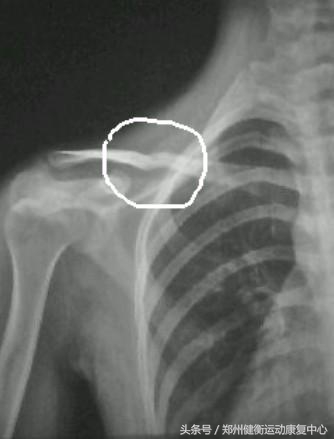

锁骨位于胸前方,是上肢带骨与躯干骨的唯一骨性连接结构。锁骨细长,部位表浅,容易受*力暴**致骨折,是最常见的骨损伤之一,常因未进行康复治疗以致动能活动障碍等。早期的进行康复治疗可以使患者功能最快、最大程度的恢复,尽早的重返社会,为家庭和社会家庭减轻负担,并为患者减轻痛苦。